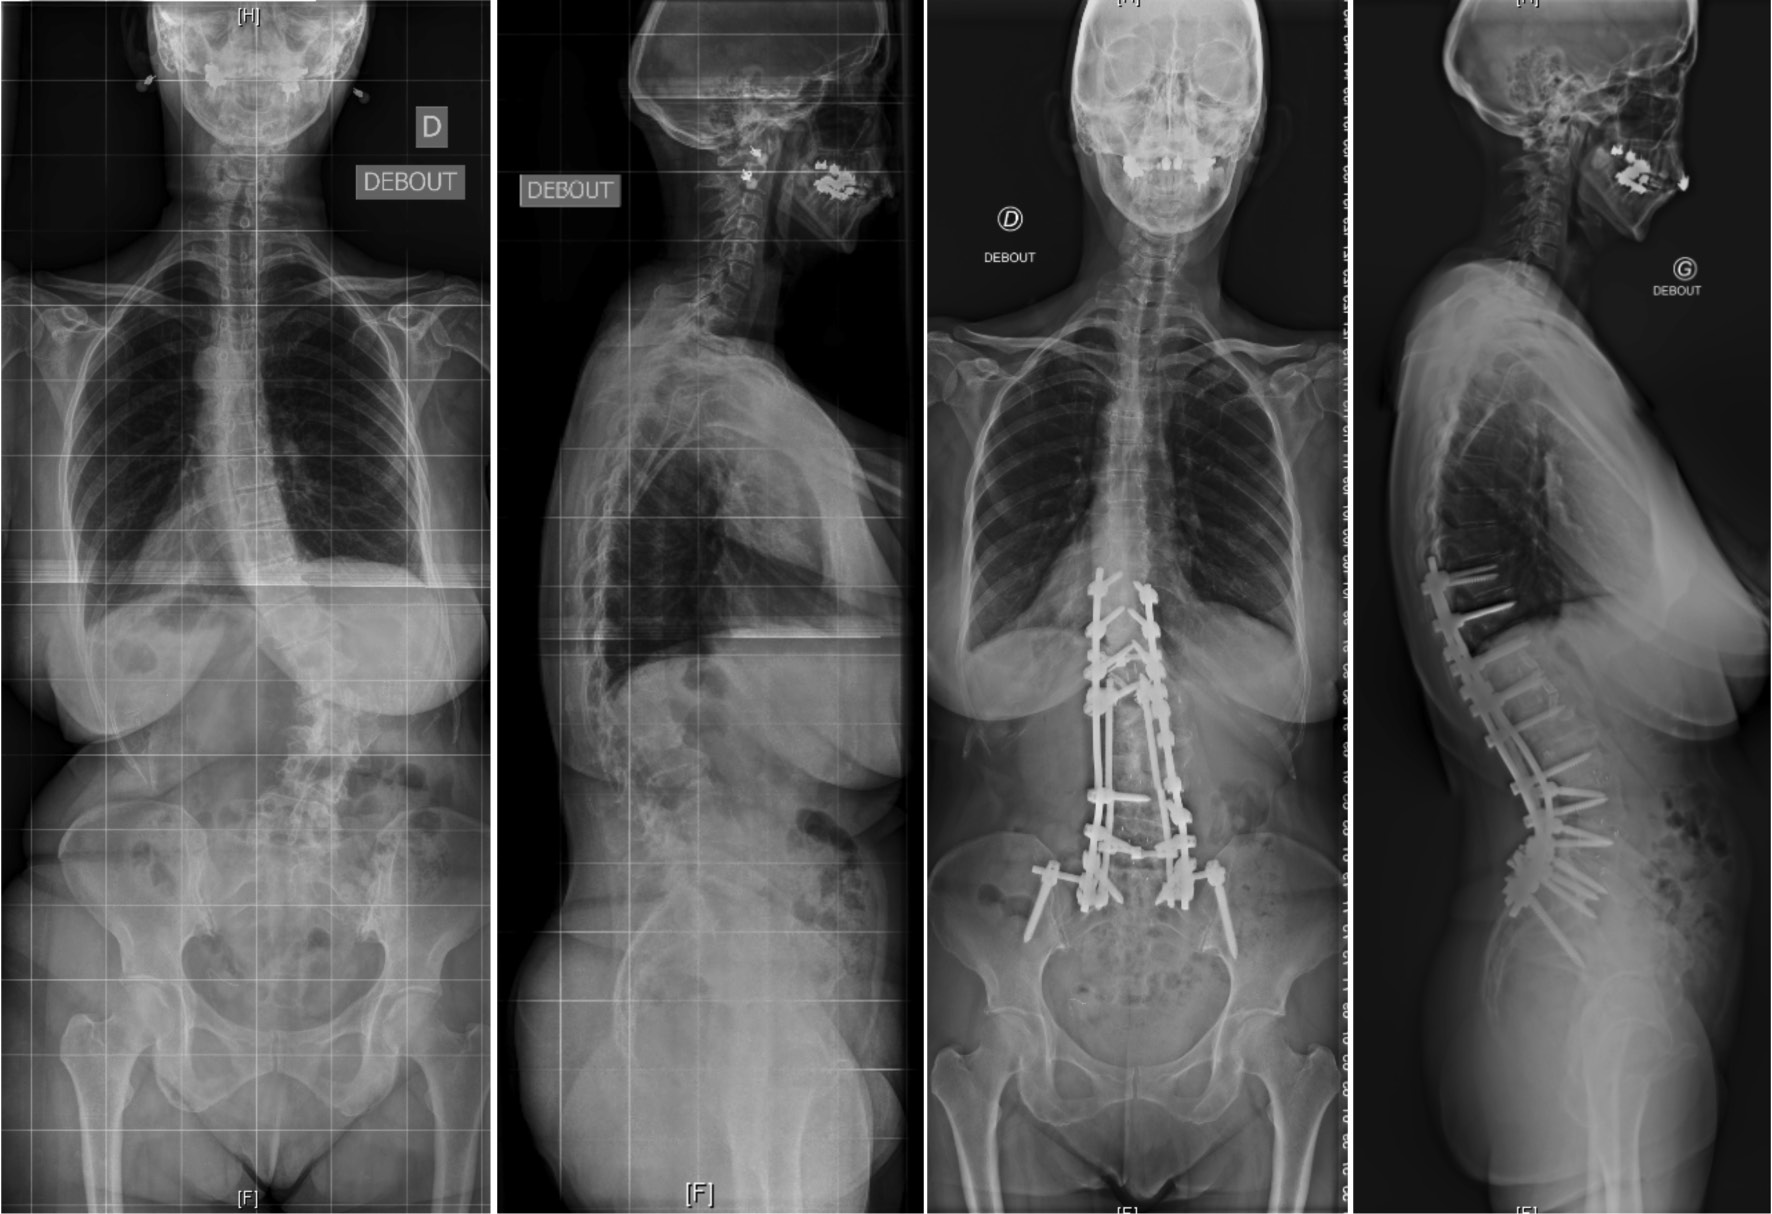

脊柱形态与症状来源

成人脊柱侧凸通常与腰椎前凸的丢失与胸腰交界处的后凸畸形有关,从而导致躯干前倾造成失平衡,此时人体往往会通过骨盆的后倾和膝关节的屈曲进行代偿。不断进展矢状面畸形最终会影响患者的健康相关的生活质量(HRQoL)。同时,由于椎旁肌的能量消耗增加以抵消身体前倾所造成的失平衡,从而导致腰背痛,肌肉劳损和活动功能障碍。

成人脊柱侧凸畸形与后凸畸形